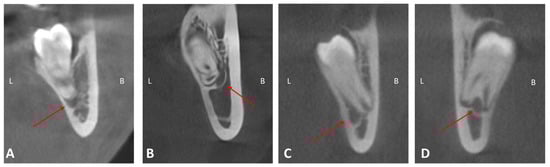

| Class I: the mandibular canal locates on the apical side | 179 | 70.8 |

| Class II: the mandibular canal locates on the buccal side | 44 | 17.4 |

| Class III: the mandibular canal locates on the lingual side | 21 | 8.3 |

| Class IV: the mandibular canal locates between the roots | 9 | 3.6 |